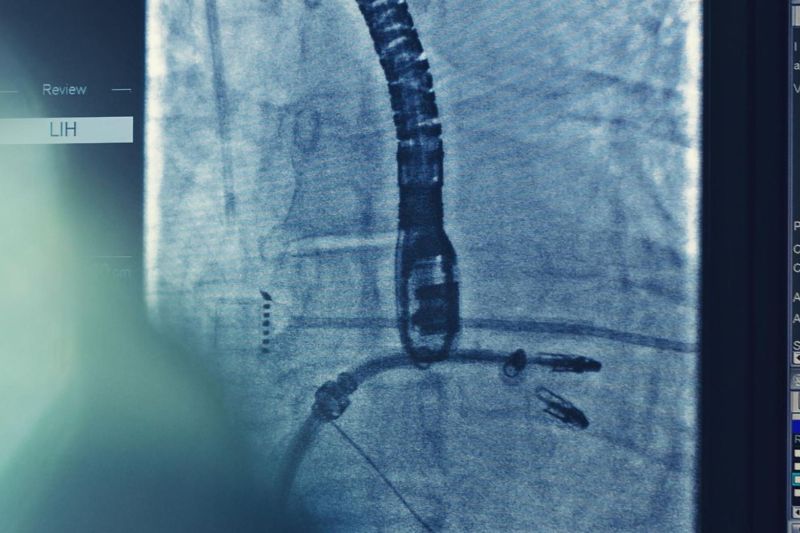

Dưới đây là một số hình ảnh hở van tim hai lá, giúp bạn hiểu rõ hơn về bệnh lý này:

Phương pháp can thiệp ít xâm lấn tiên tiến hiện nay là sửa van 2 lá qua da (MitraClip). Kỹ thuật này không yêu cầu mở ngực hay ngừng tim tạm thời, thích hợp cho người bệnh nặng.

Bác sĩ sẽ tiếp cận van hai lá bằng một ống thông được dẫn qua tĩnh mạch ở chân, đi đến tim. Sau đó, một thiết bị kim loại được đưa vào để kẹp lại hai mép van bị hở, giúp van đóng kín, ngăn ngừa máu trào ngược vào tâm nhĩ trái, cải thiện chức năng tim.